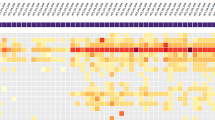

Hybrid capture shotgun sequencing

The forty-one CSF samples, along with one enterovirus-positive CSF used as a control, and four negative controls were shotgun sequenced and processed using the CZ ID metagenomics pipeline v8.2. Average reads per sample were 43.47 million, with an average of 13.18 million reads passing filters (host and low quality) per sample. Significant parameter detection was achieved in 22 CSF samples using four negative controls in a background model computed on the CZ ID pipeline. A Z-score of 100 indicates that the virus was not detected in negative controls. HERV-K113 was detected in 13 CSF samples by the PikaVirus pipeline, of which 9 showed co-detection with other viruses. It is noteworthy that the CZ ID pipeline did not detect HER-K113 in any sample, presumably because this virus is considered a part of the human genome. Significant results from the CZ ID metagenomics pipeline v8.2 are shown in Table 1. Virus detection was further confirmed by specific PCR in three HHV-7, one BKV, and one EBV cases.

Other viruses were detected in 17 CSF samples. However, these hits were dismissed as feasible results because they were also present in the negative controls, resulting in scores far from 100 according to the CZ ID background model generation. Nonetheless, PCR testing was conducted when available, revealing the detection of human papillomavirus 115 in one CSF sample and additional HERV-K113 detections in four of these samples. Data from these non-relevant detections are shown in Table 2.

HCSS proved to be a successful approach for detecting both RNA and DNA viruses in CSF from children with meningoencephalitis of unknown aetiology. Compared to the standard-of-care screening using the FilmArray Meningitis/Encephalitis (FA/ME) panel, HCSS achieved additional significant viral detection in 30 cases, some of which were not included in the FA/ME panel. These detections included six cases of parechovirus A, three of enterovirus ACD, three of HHV-7, two of BK virus, four of polyomavirus 5, one of HSV-1, one of VZV, two of CMV, one of EBV, one of influenza A virus, and one of rhinovirus by using CZ ID pipeline. In addition, 13 detections of HERV-K-113 by using Pika Virus pipeline were found. Of all these, one sample with BKV, three with HHV-7, one with EBV, and all with HERV-K-113 were further confirmed by PCR.